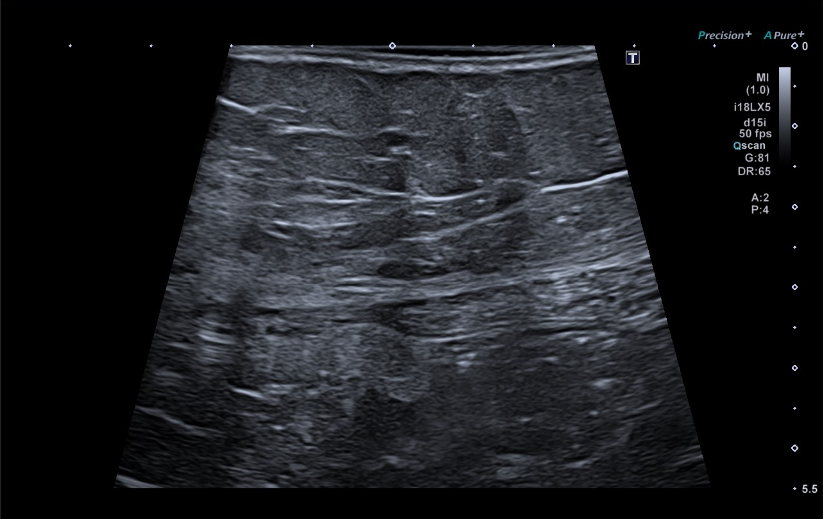

Se realiza una ecografía abdominal en el centro de salud visualizándose una masa hiperecogénica de 15 centímetros, aproximadamente, que parece dependiente del riñón derecho.

Se deriva a la paciente a urgencias hospitalarias donde se realiza una analítica sin objetivarse hallazgos significativos y una nueva ecografía en la que se visualiza una gran formación quística en flanco derecho que impresiona depender del riñón derecho. De manera ambulatoria se realizan un TC toraco-abomino-pélvico y una RMN abdomino-pélvica hallándose una masa abdomino-pélvica derecha de 15 x 13,5 x 12 centímetros de diámetros transversal, craneocaudal y anteroposterior, respectivamente, que impresiona de origen retroperitoneal vs origen ovárico.